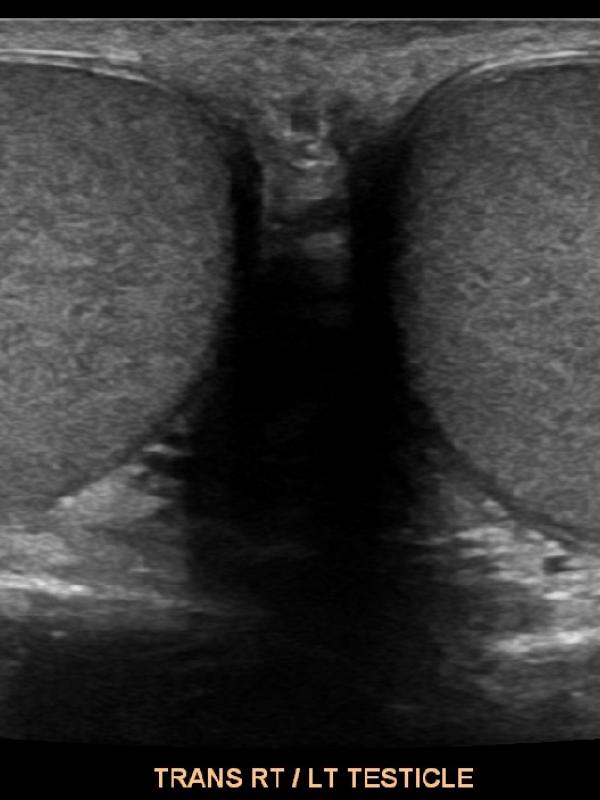

Scrotal ultrasound

Ultrasound imaging is the primary diagnostic modality used to evaluate the scrotum/testicles. Referring providers will order a scrotal ultrasound for a number of reasons. The most common reasons are: testicular pain, a lump is discovered, or if a hernia is suspected. Undescended testis.